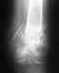

Здравствуйте .Помогите пожалуйста с ответом. 2 года назад у меня была операция Артородез голеностопного сустава и малоберцовой кости . Врачи сказали что через 7 лет я не смогу ходить . Сейчас я хожу нормально и боли почти не чувствую.Но голностоп не двигается на 100%. Скажите пожалуйста есть ли какие то альтернативы , что вообще возможно сделать ? может за границей проводятся какие-нибудь операции ? Заранее спасибо.

Голеностоп не двигаетя именно потому, что сустав артродезирован, замкнут. Не знаю, кто и почему сказал насчет 7 лет. Обычно после замыкания этого сустава люди ходят, пока вообще ходят.

Теоретически можно рассмотреть вопрос о размыкании с установкой искусственного голеностопного сустава, но без предыстории, зачем замкнули, и доскональной оценки состояния этой области, сейчас разговор беспредметный.

Да и не будем забывать, что "нет такого состояния, которое нельзя было бы ухудшить операцией". То есть пока Вы "ходите нормально и боли почти не чувствуете", представляется, что от добра добра искать не надо - ходите себе дальше. Пользуйтесь амортизирующей обувью типа кроссовок, помня о том, что рессорная функция стопы уменьшилась.